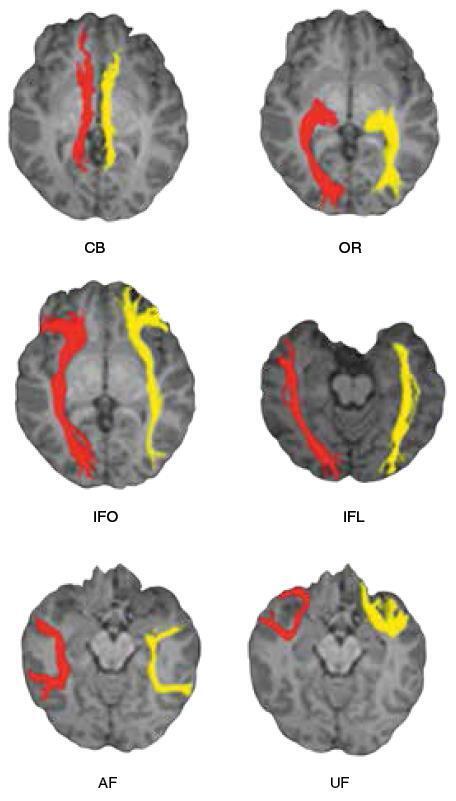

Давайте ещё раз взглянем на латерализацию функций в полушариях головного мозга, которую предлагают исследователи из Пекинского педагогического университета по руководством профессора Ни Шу, создавшие с помощью диффузно-тензорной трактографии схему анатомических связей, обеспечивающих межполушарную асимметрию человеческого мозга (рис. 53)94.

Рис. 53.  Схема структурной асимметрии основных трактов белого вещества в полушариях головного мозга: СВ — связи поясной извилины, OR — зрительный тракт, IFO — нижний лобно-затылочный пучок, IFL — нижний продольный пучок, AF — дугообразный пучок, UF — крючковидный пучок.

Преобразования полушарий, вызванные латерализацией функций, как показывает данное исследование, буквально перестраивают мозг на анатомическом уровне.